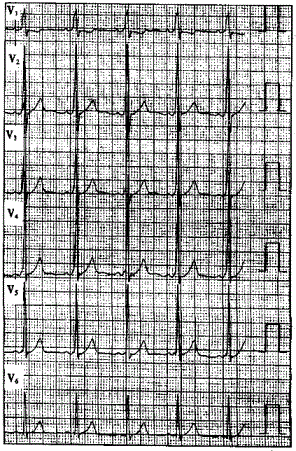

问题 患者男性,40岁,多次发作心悸,心电图一-见下图,显示为预激图形。 ? ? 该心电图提示旁路位于

选项 A.左后间隔 B.左侧壁 C.右后间隔 D.右前壁 E.右侧壁

答案 B

解析 :食管心房调搏可以诱发心动过速并确定心动过速的发生机制该心电图显示V导联delta波向上,旁路位于左侧;Ⅱ、Ⅲ、aVF导联delta波向上,提示旁路位于左侧壁;当旁路前传有效不应期<270ms或预激综合征合并心房颤动时最短RR间距≤240ms时,提示为高危旁路;逆向型房室折返性心动过速的折返途径为:心房→旁路→心室→房室结→心房